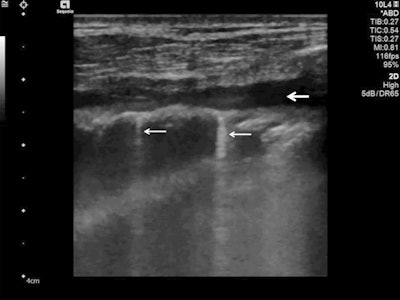

Lung ultrasound using a linear probe. B-lines (white arrows) with irregular pleura and a small pleural effusion (bold white arrow).

Lung ultrasound using a linear probe. B-lines (white arrows) with irregular pleura and a small pleural effusion (bold white arrow).Lung ultrasonography can be used for quick evaluation of the severity of SARS-CoV-2 pneumonia, to track the evolution of disease during follow-up, and to monitor lung recruitment manoeuvres. Additionally, ultrasonography can track the response to prone-position ventilation and the controlling of extracorporeal membrane therapy.